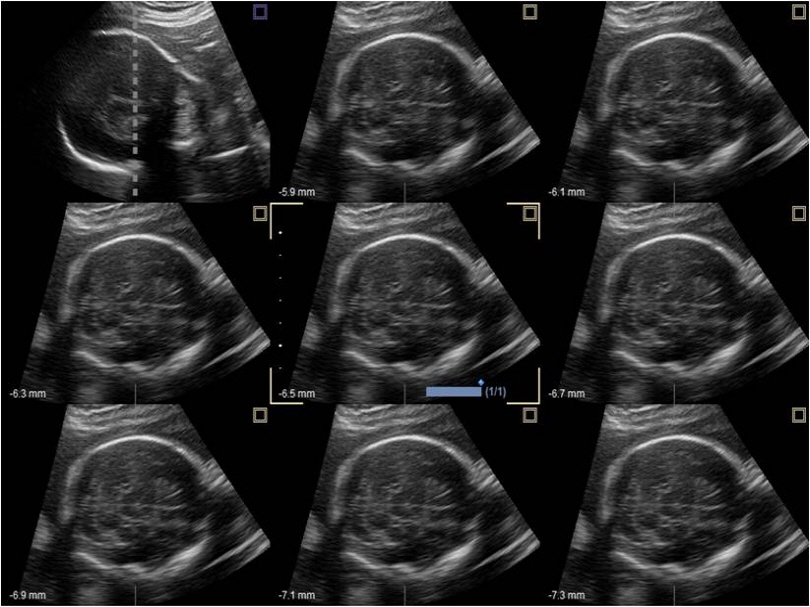

VC1-6T

Volume Convex (1-6MHz)

Application:

Abdomen, OB, GYN, EM

VE3-10H

High density volume endocavity transducer (3-10MHz)

Application:

GYN, OB, Urology, EM